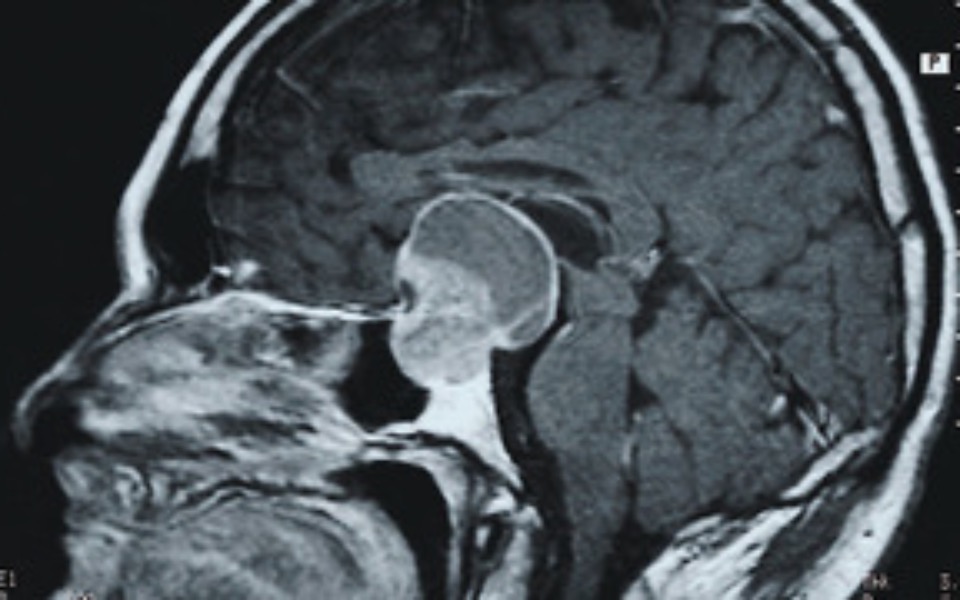

leczenie rak muzgu

Zbieramy pieniądze na raka muzgu każda złotówka się liczy pomóżcie prosze